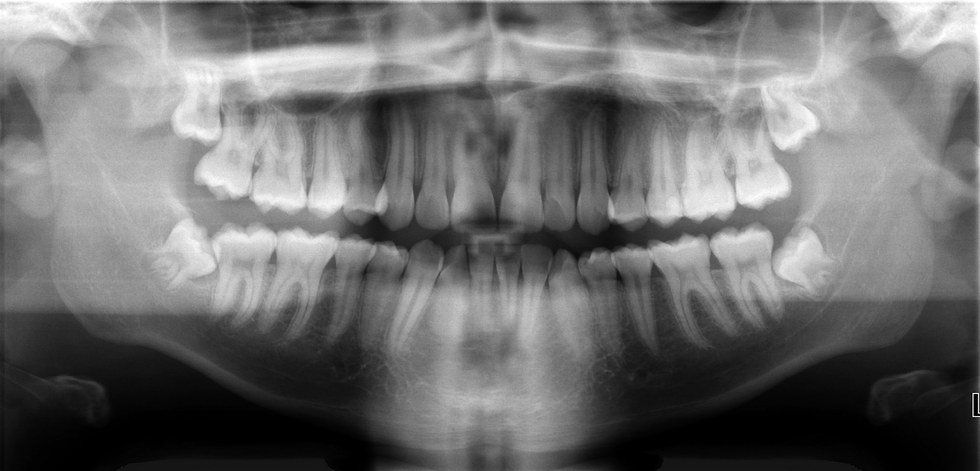

Forensics dentistry dates back to 1692 during the Salem Witch Trials when an accused "witch" was convicted by comparing their bite print with those found on victims. This type of identification is possible because the lack of or presence of dental hygiene effects the structure and appearance of teeth. As well as missing teeth, fractures, and malformed teeth all bear their own unique characteristics that show when a bite mark is examined.

Forensic dentistry is an acceptable form of evidence when used in a well developed case because of how precise and accurate it can be in identifying assailants. Forensic dentists are trained to identify the bite marks for their various impressions and types. The superior training received by these dentist and strict guidelines they must follow makes this area of forensics wildly accredited.